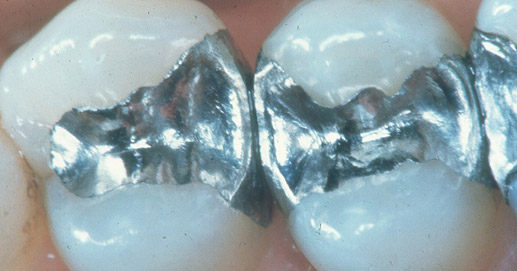

Purtroppo il mercurio viene tutt’oggi utilizzato spesso nell’amalgama dentale: un composto che viene impiegato per realizzare le otturazioni.

Oggi il numero delle otturazioni realizzate ancora in amalgama è decisamente eccessivo: infatti, al di sopra delle 2 otturazioni in amalgama, c’è un’assunzione di mercurio superiore alla soglia stabilita dall’OMS (Organizzazione Mondiale della Sanità).

La rimozione delle otturazioni in amalgama richiede un’attenzione speciale perché prevede l’utilizzo del trapano ed è, quindi, a rischio di vaporizzazione del mercurio e di conseguente esposizione ai rischi di un’intossicazione.